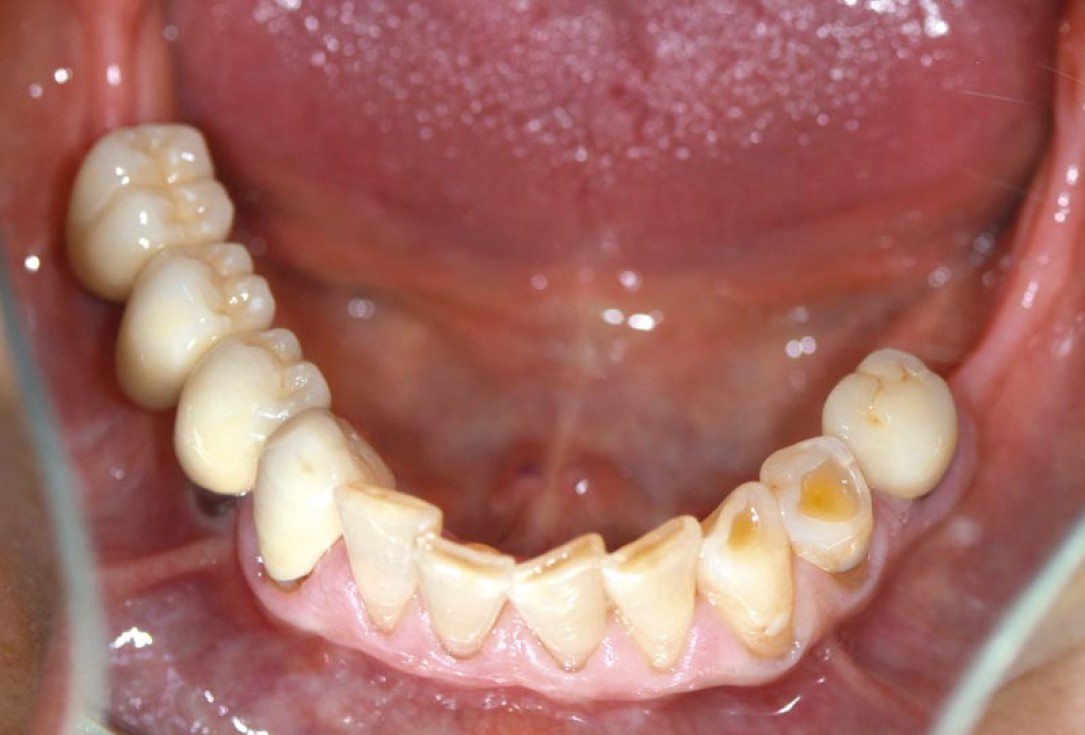

14/14 - Final clinical situation with prosthetics 18 months post augmentation

Block augmentation with maxgraft® in the mandible - PD Dr. Dr. F. Kloss